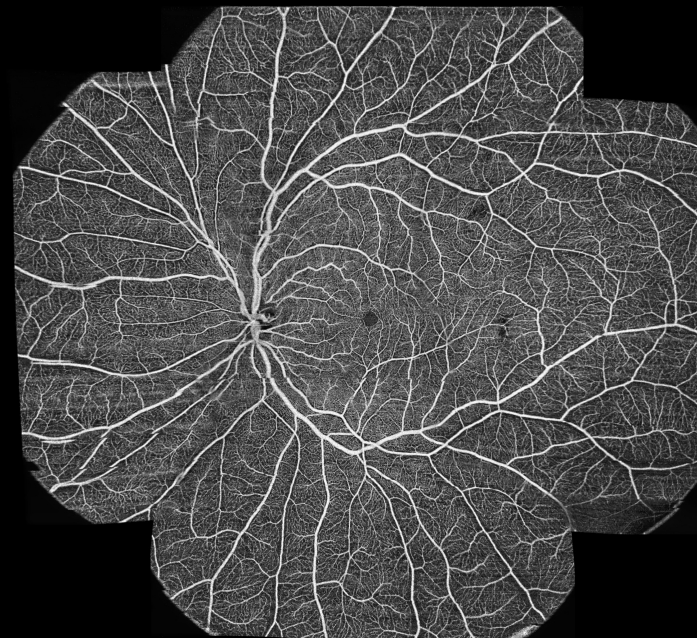

Cette exploration rétinienne par OCT en coupe peut être complétée par une exploration en OCT-Angiographie (cf fiche) ou par OCT du nerf optique ou du segment antérieur en fonction des résultats obtenus ou de la demande d’examen faite par votre ophtalmologiste traitant. Le cumul des zones d’exploration allonge la durée de l’examen.